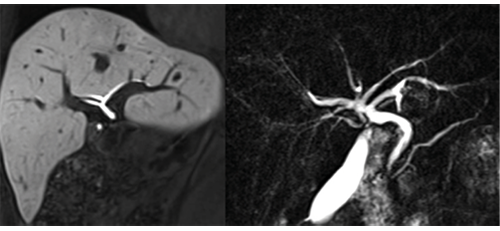

Biliary anatomy displayed with MR cholangiographic (MRCP) (left) and gadoxetic acid enhanced MRCP in a liver donor.

Biliary anatomy displayed with MR cholangiographic (MRCP)